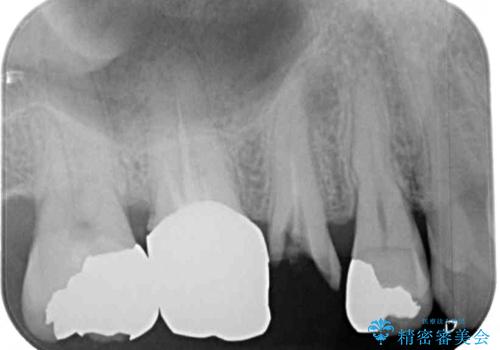

レントゲン写真から、特に大きなむし歯などは認められませんでしたが、根管治療があまり十分に行われているとは言えない状態でした。

まずは仮歯を装着し、根管治療を行った上で土台を植立し、オールセラミッククラウンにて補綴治療を行うこととしました。